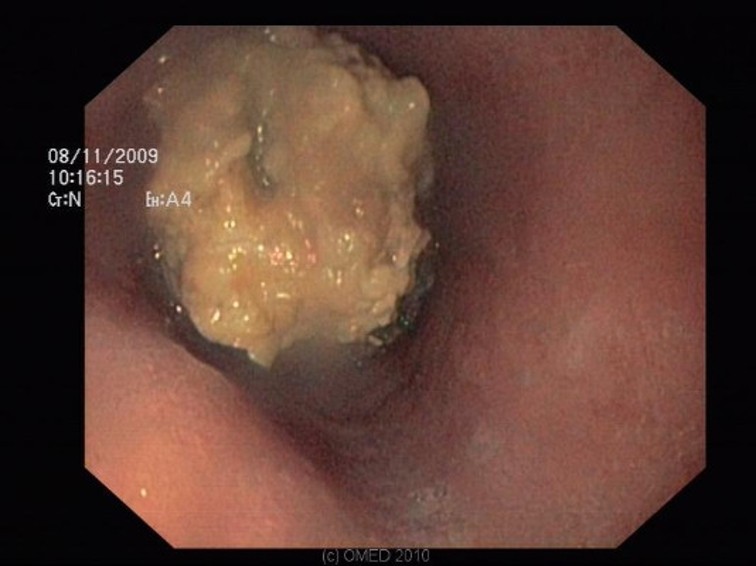

Endoscopy - oesophageal FB, impacted lamb meat in distal oesophagus